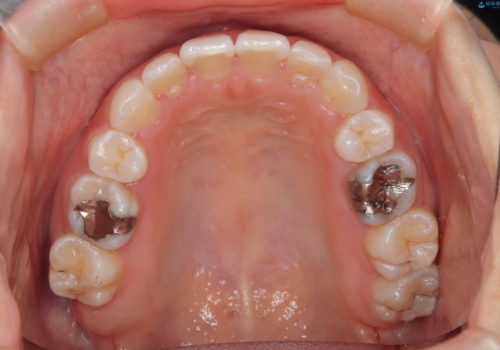

- 子供のころに矯正治療をされていたが、後戻りをしてしまったという20代女性の患者様です。上顎左右の2番が、咬合時に下顎の歯よりも内側に入っているクロスバイトという状態でした。奥歯の咬合関係は変えずに、マウスピース矯正にて前歯の並びを綺麗なアーチに仕上げました。再度後戻りしてしまうリスクを軽減させるために、リテーナー(保定装置)をお渡ししています。

リテーナーについて

矯正治療後は後戻り防止のために、リテーナー(保定装置)を装着していただきます。目安は半年は昼も夜も、半年以降は夜のみと指示させていただくことが多いですが、症例ごとに決定していきます。